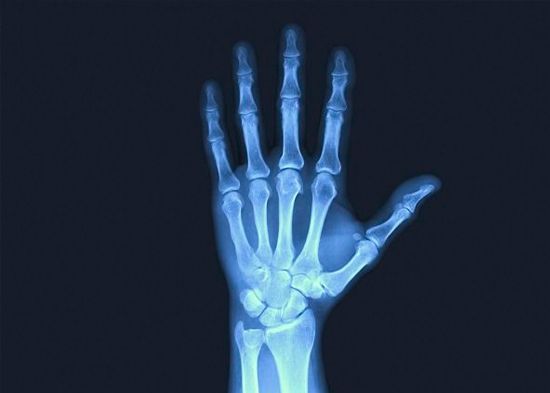

La nutrición juega un papel fundamental en el desarrollo y mantenimiento de la salud ósea. Los huesos son órganos porosos altamente vascularizados que reciben oxígeno y nutrientes a través de una red de poros interconectados por canales delgados que están incrustados en los huesos. El transporte eficiente de nutrientes dentro de estos microsistemas es vital para mantener los huesos fuertes y saludables.

El hueso compacto forma la capa dura y exterior del hueso. Si lo vieras bajo un microscopio, verías que está lleno de pequeños conductos o canales para los nervios y vasos sanguíneos. Estos vasos sanguíneos suministran constantemente nutrientes esenciales como calcio, fósforo, vitamina D, magnesio, potasio, fluoruro, proteínas y varias otras vitaminas y minerales necesarios para la formación ósea y los procesos metabólicos.

El hueso esponjoso es ligero pero fuerte, y se encuentra principalmente en los extremos de los huesos y las articulaciones. Tiene forma de panal y está lleno de secciones abiertas llamadas poros que contienen la médula ósea, nervios y vasos sanguíneos que transportan nutrientes hacia y desde el hueso.